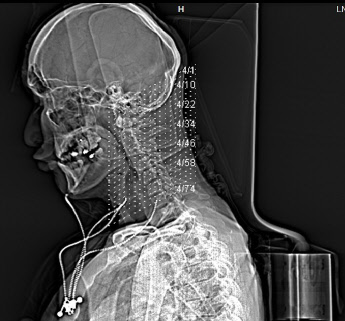

Anbei Daten zur Enthauptung (Heilige Schrift)

Jefferson Fraktur (med. Fachsprache)

Das Bild bekam ich erst vor kurzem

Ist vom 20.11.2017

Bohrlochtrepernation